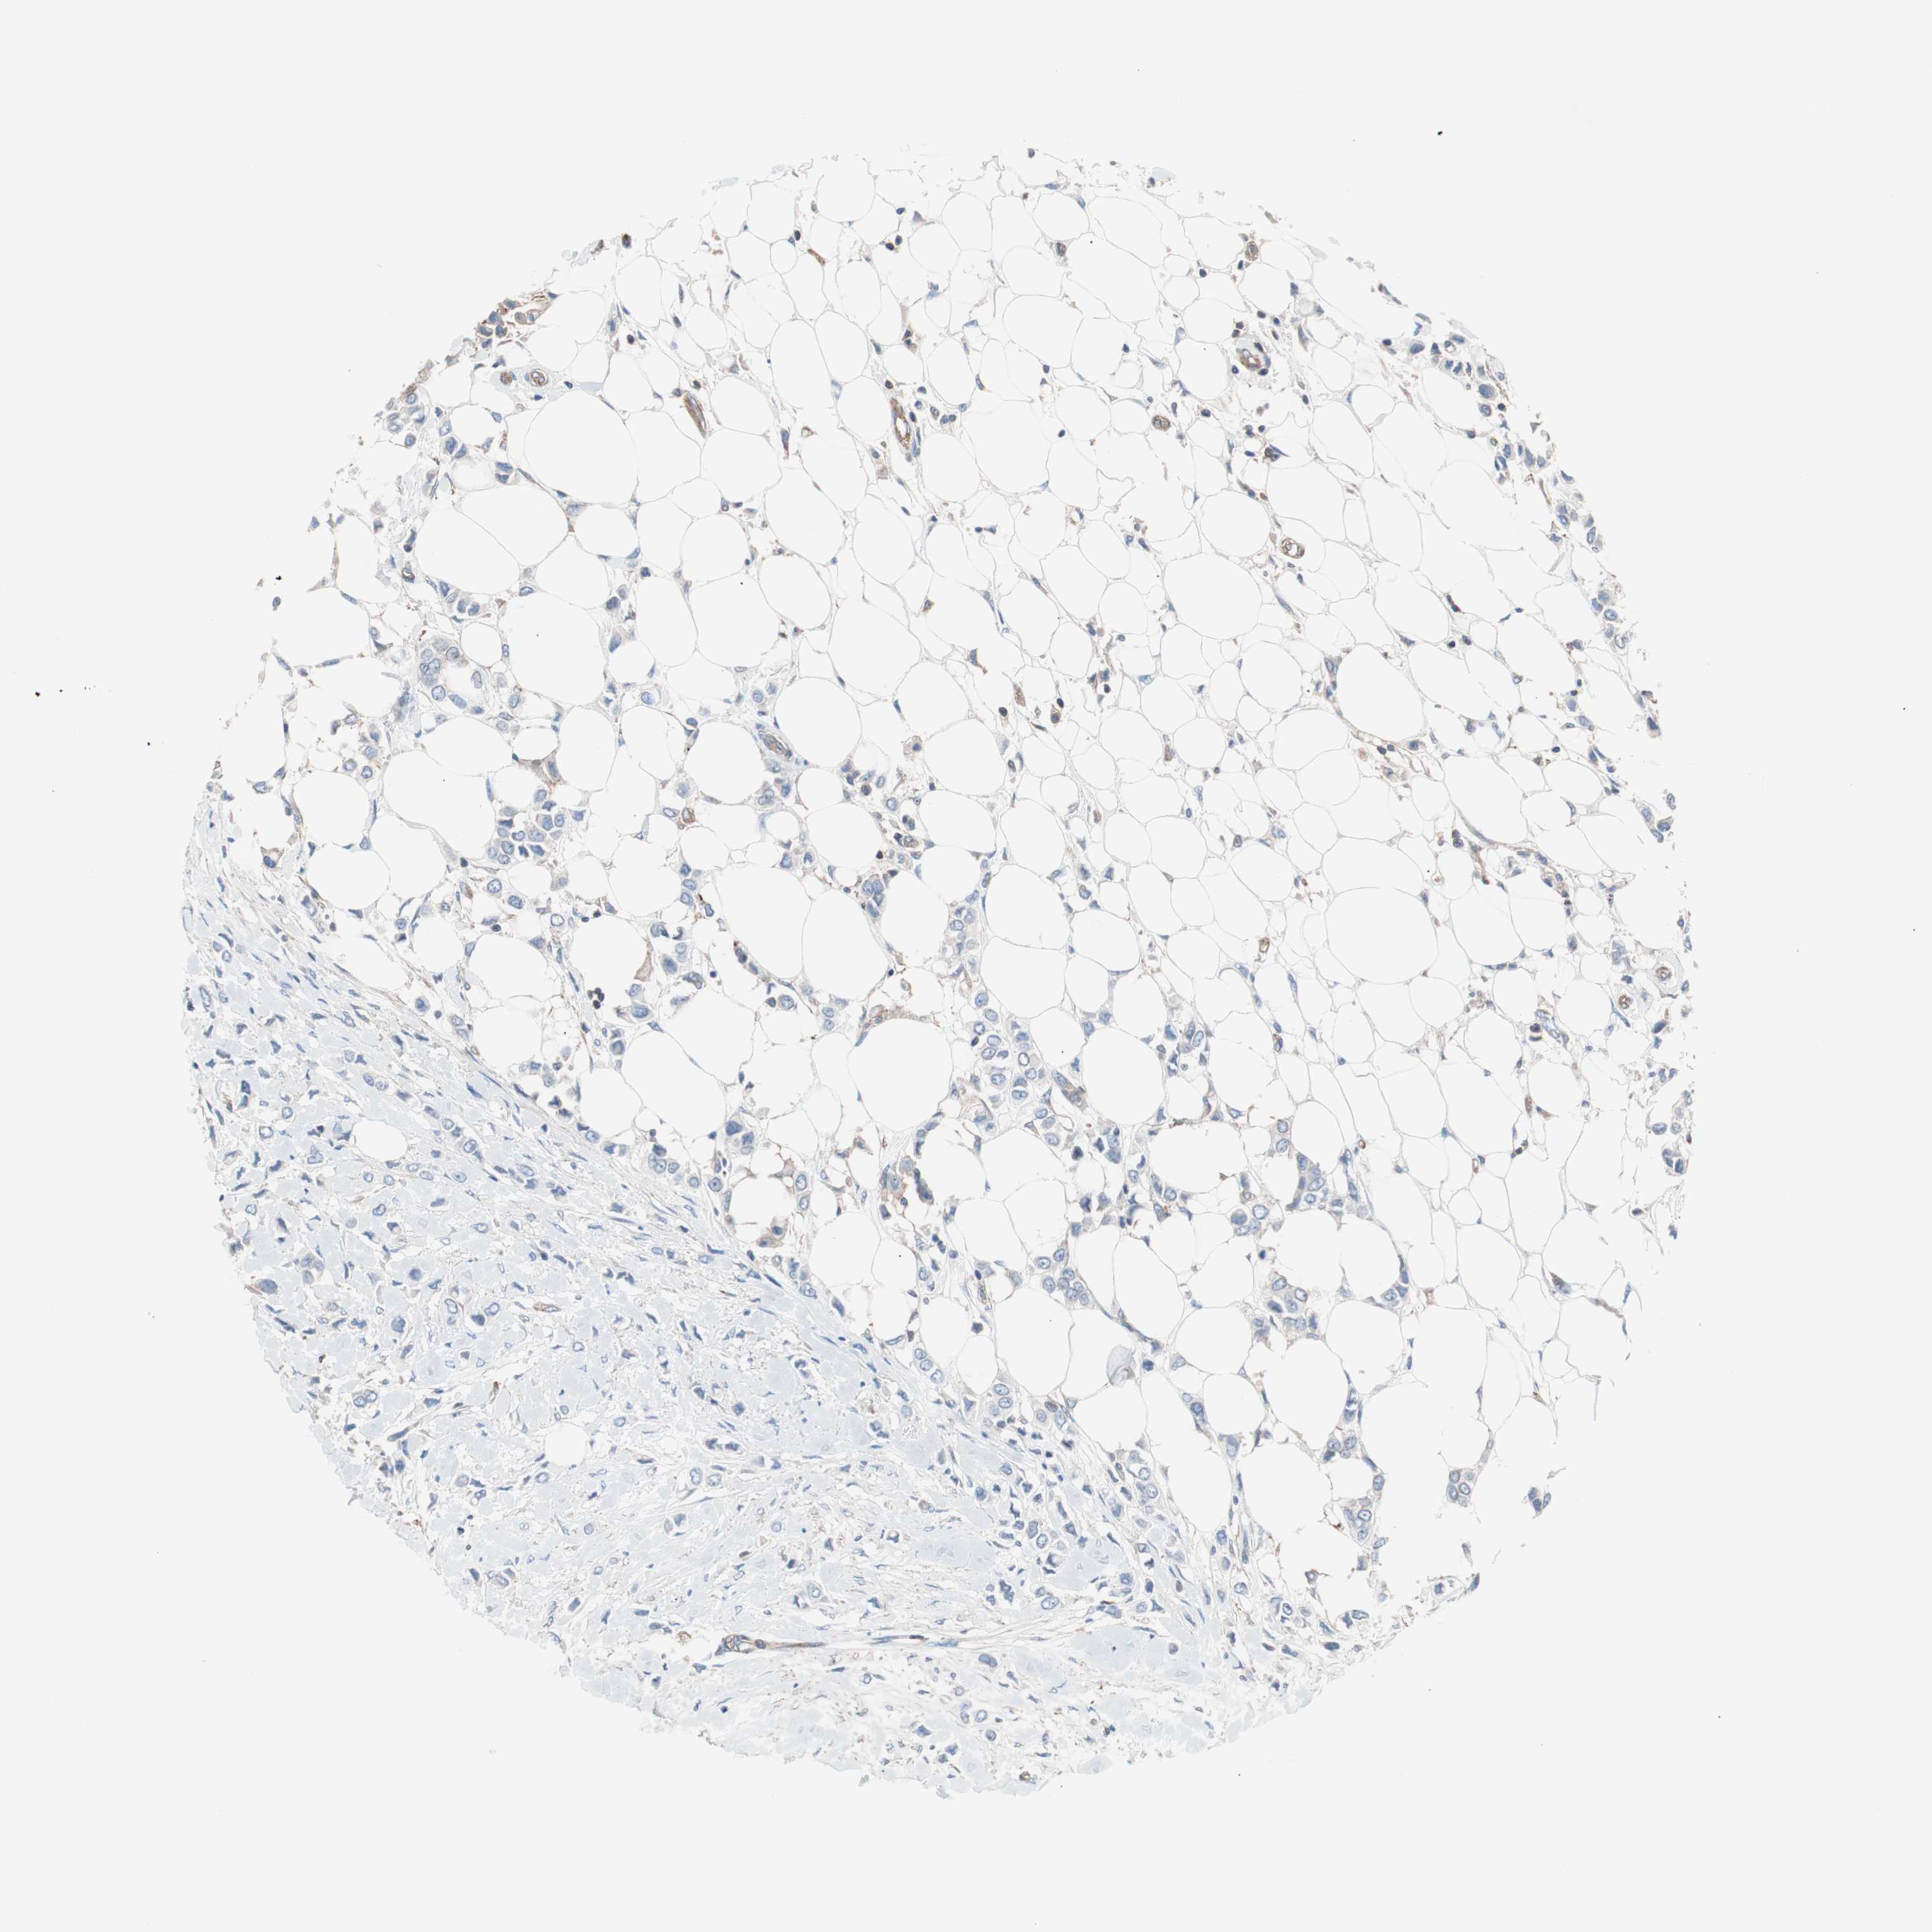

CANCER BREAST CANCER Show tissue menu

BRCA TCGA BRCA VALIDATION PROTEIN EXPRESSION